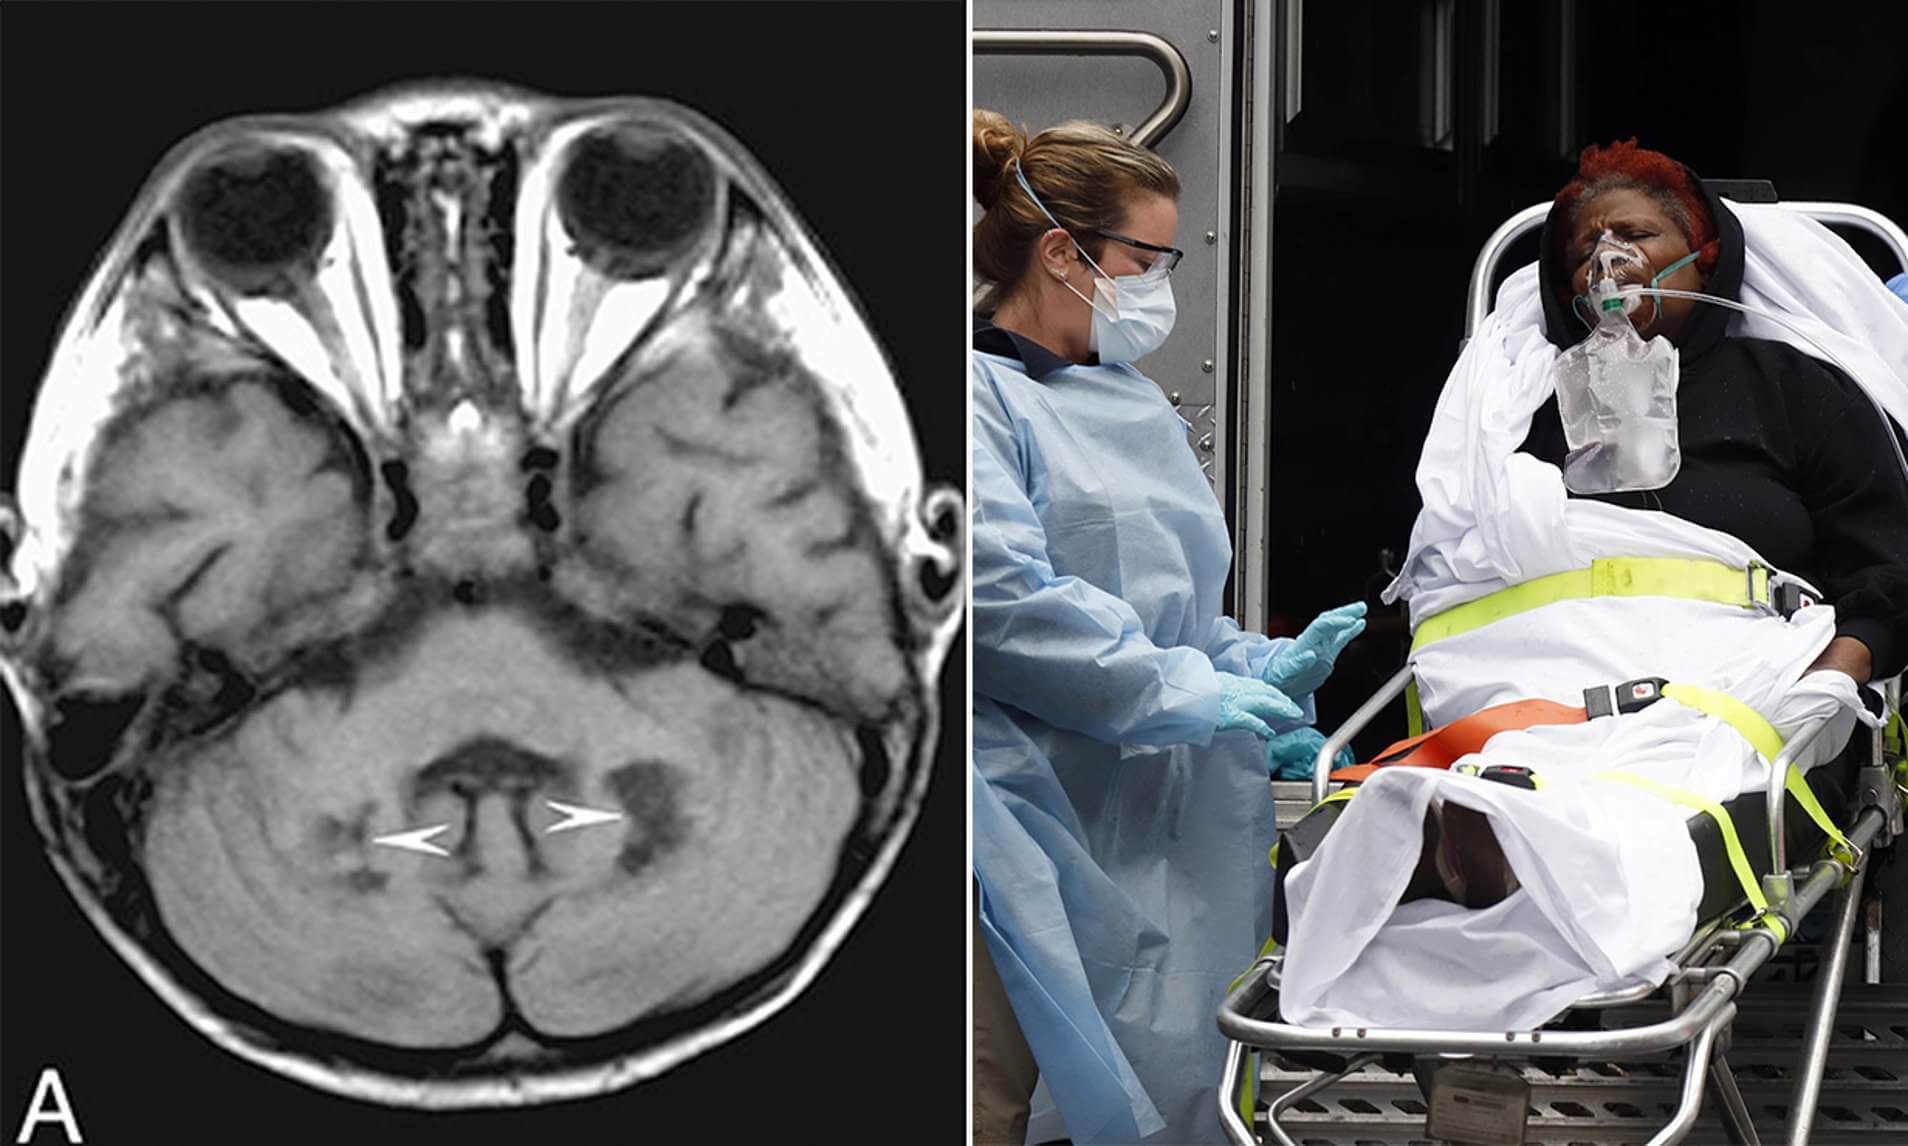

В других случаях исследования описывали тяжелый энцефалит у больного CоVID-19 (воспаление и отек головного мозга) и инсульт у здоровых молодых людей с легкими симптомами CоVID-19. На эту особенность нового коронавируса обратили внимание ученые из Китая и Франции и исследовали распространенность неврологических расстройств у пациентов CоVID-19. Полученные результаты показали, что 36% пациентов имеют неврологические симптомы. Многие из этих симптомов были легкими и проявлялись головной болью или головокружением, которые могли быть вызваны сильным иммунным ответом организма. Но также были замечены и другие более специфические и тяжелые симптомы, включающие потерю обоняния или вкуса, мышечную слабость, инсульт, судороги и галлюцинации.

Так выглядят сканы МРТ

Исследователи отмечают, что эти симптомы чаще наблюдаются в тяжелых случаях, причем оценки варьируются от 46% до 84% случаев, с выраженными неврологическими симптомами. Изменения сознания, такие как дезориентация, невнимательность и двигательные расстройства, также наблюдались в тяжелых случаях и сохранялись после выздоровления. Но почему это происходит?